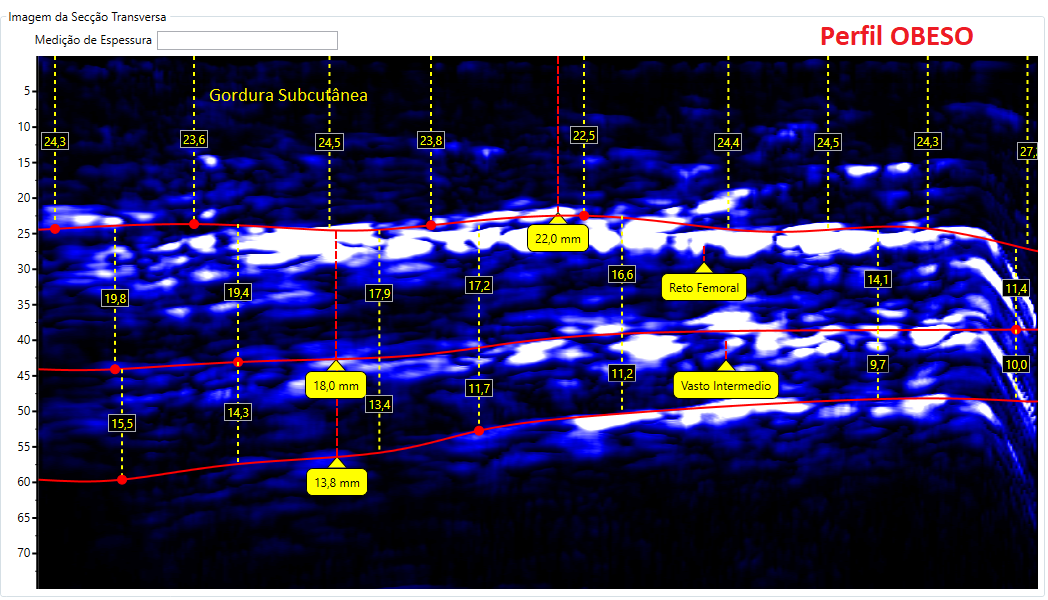

Comparativos de imagens de Coxa